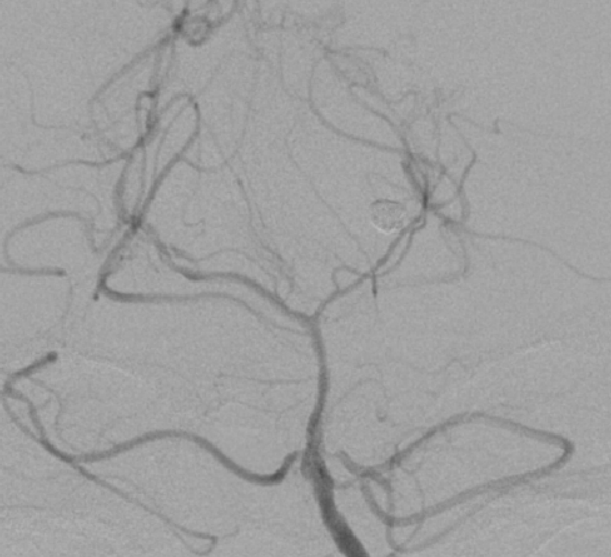

??动脉瘤栓塞完全

??在多科室的密切合作下,周垂贤主任凭借精湛的手术技能,成功实施颅内动脉瘤介入栓塞手术,将动脉瘤完全栓塞,手术第一阶段顺利完成。手术第二阶段,经过术前严密规划,神经外科团队在机器人引导下实施脑立体定向血肿碎吸手术,机器人协助让手术效率大大提升,术中抽出血肿29毫升。整个手术在2小时内顺利完成。